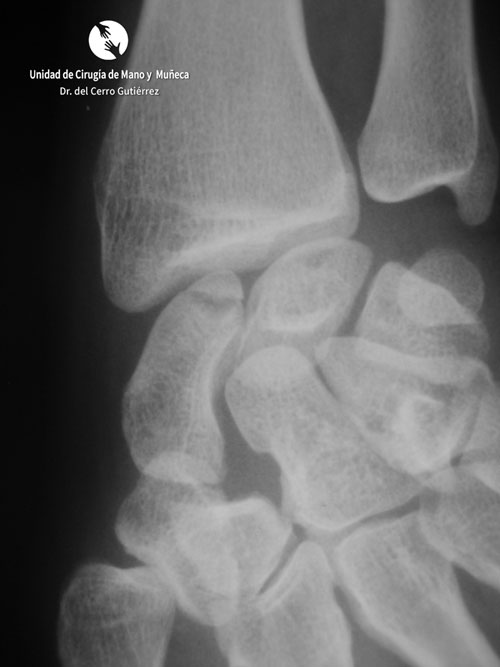

Pseudoartrosis del tercio medio

Fractura del Escafoides Pseudoartrosis del tercio medio

Fractura del escafoides. Pseudoartrosis del tercio medio

Pseudoartrosis. Inestabilidad Dorsal del Segmento Intermedio. DISI